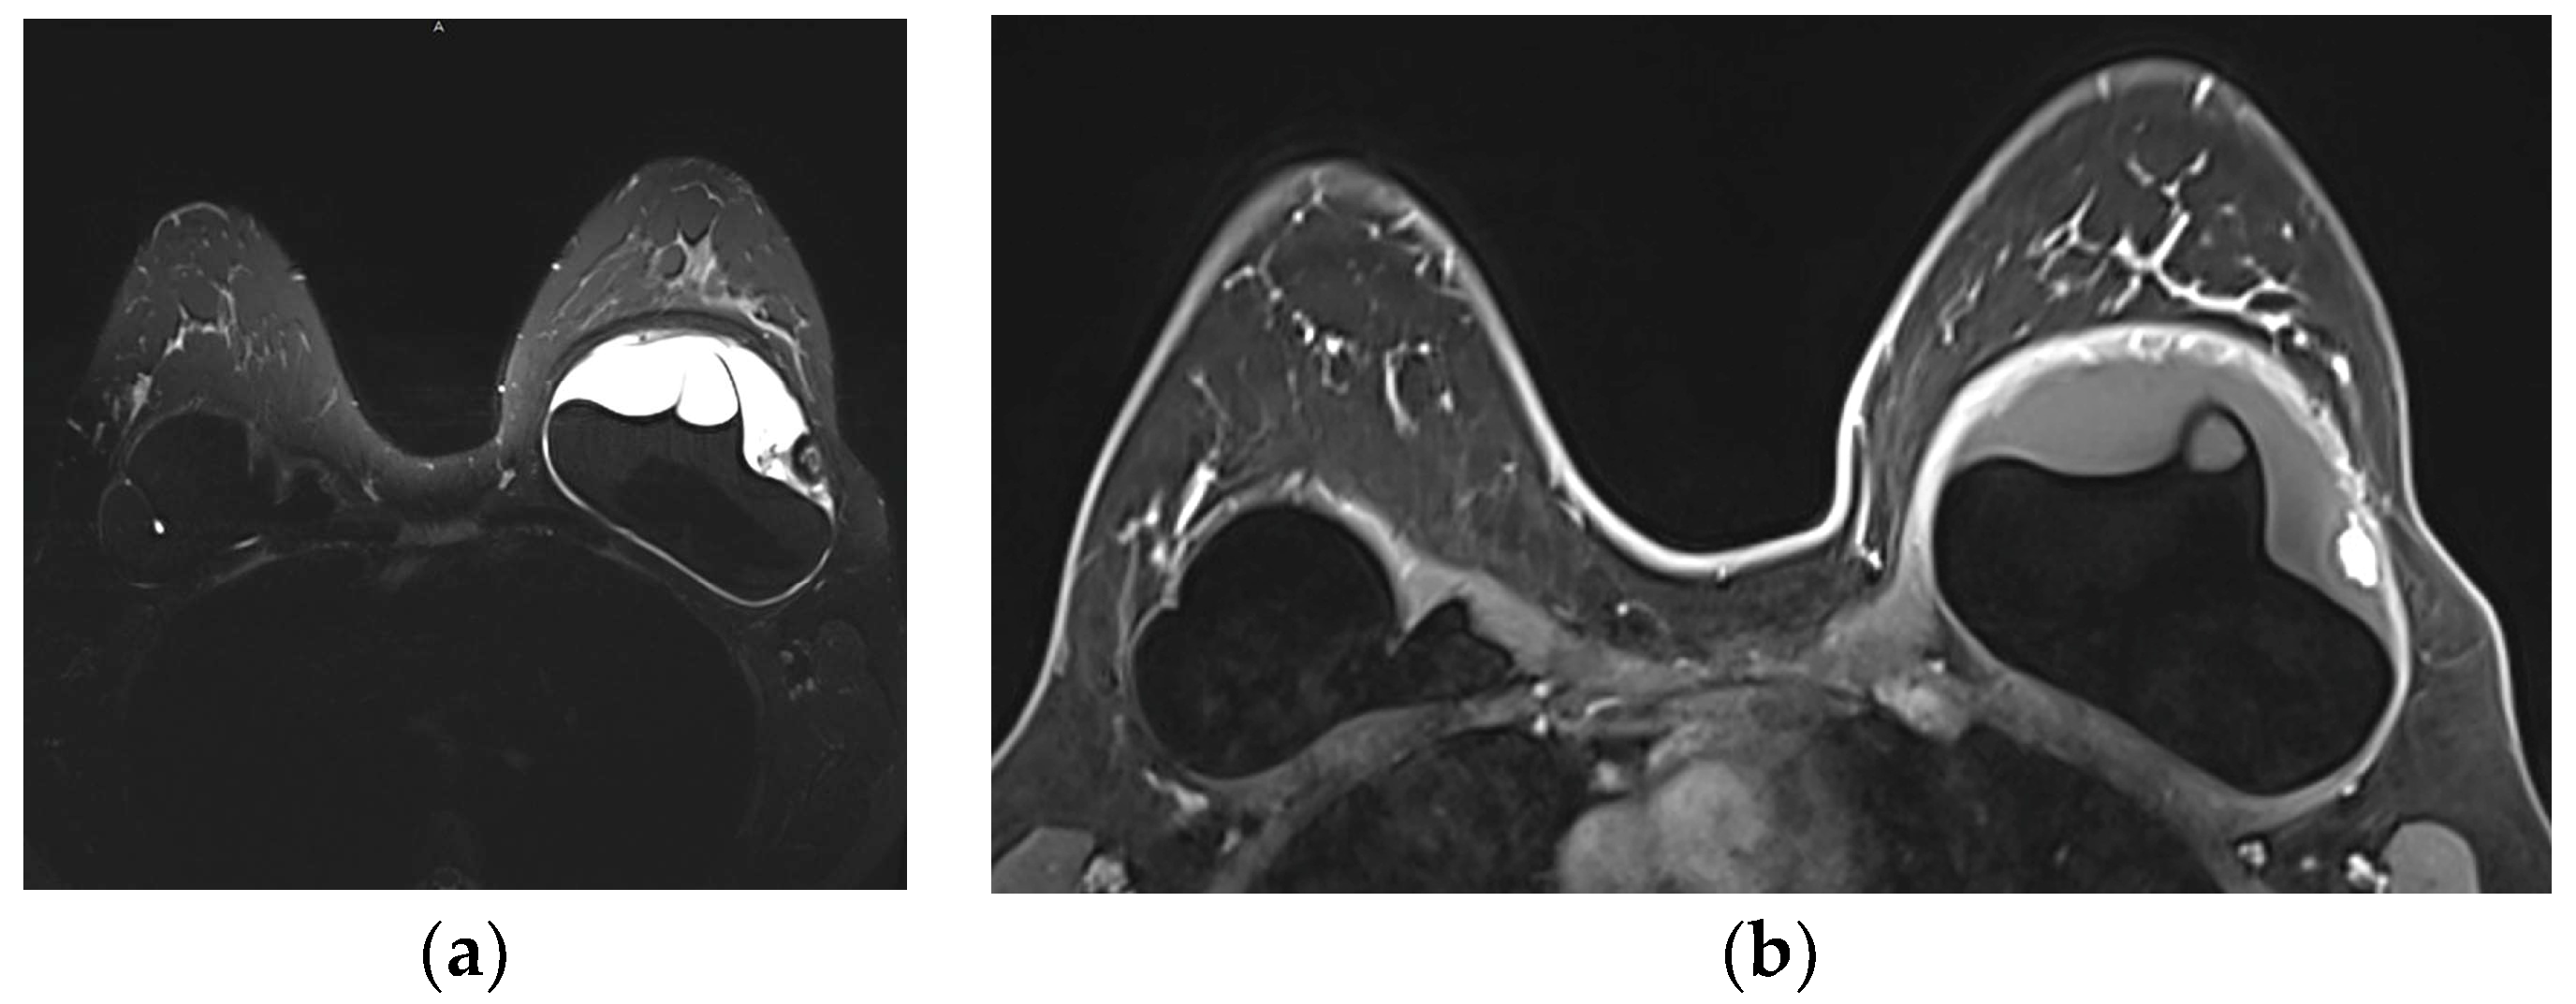

5.2.5. Implant Rupture

- Venkataraman, S.; Hines, N.; Slanetz, P.J. Challenges in mammography: Part 2, multimodality review of breast augmentation—Imaging findings and complications. Am. J. Roentgenol. 2011, 197, W1031–W1045. [Google Scholar] [CrossRef] [PubMed]

- Wong, T.; Lo, L.W.; Fung, P.Y.; Lai, H.Y.; She, H.L.; Ng, W.K.; Kwok, K.M.; Lee, C.M. Magnetic resonance imaging of breast augmentation: A pictorial review. Insights Imaging 2016, 7, 399–410. [Google Scholar] [CrossRef] [PubMed]

- Norena-Rengifo, B.D.; Sanin-Ramirez, M.P.; Adrada, B.E.; Luengas, A.B.; Martinez de Vega, V.; Guirguis, M.S.; Saldarriaga-Uribe, C. MRI for Evaluation of Complications of Breast Augmentation. Radiographics 2022, 42, 929–946. [Google Scholar] [CrossRef]

- Green, L.A.; Karow, J.A.; Toman, J.E.; Lostumbo, A.; Xie, K. Review of breast augmentation and reconstruction for the radiologist with emphasis on MRI. Clin. Imaging 2018, 47, 101–117. [Google Scholar] [CrossRef]

- Seiler, S.J.; Sharma, P.B.; Hayes, J.C.; Ganti, R.; Mootz, A.R.; Eads, E.D.; Teotia, S.S.; Evans, W.P. Multimodality Imaging-based Evaluation of Single-Lumen Silicone Breast Implants for Rupture. Radiographics 2017, 37, 366–382. [Google Scholar] [CrossRef] [PubMed]